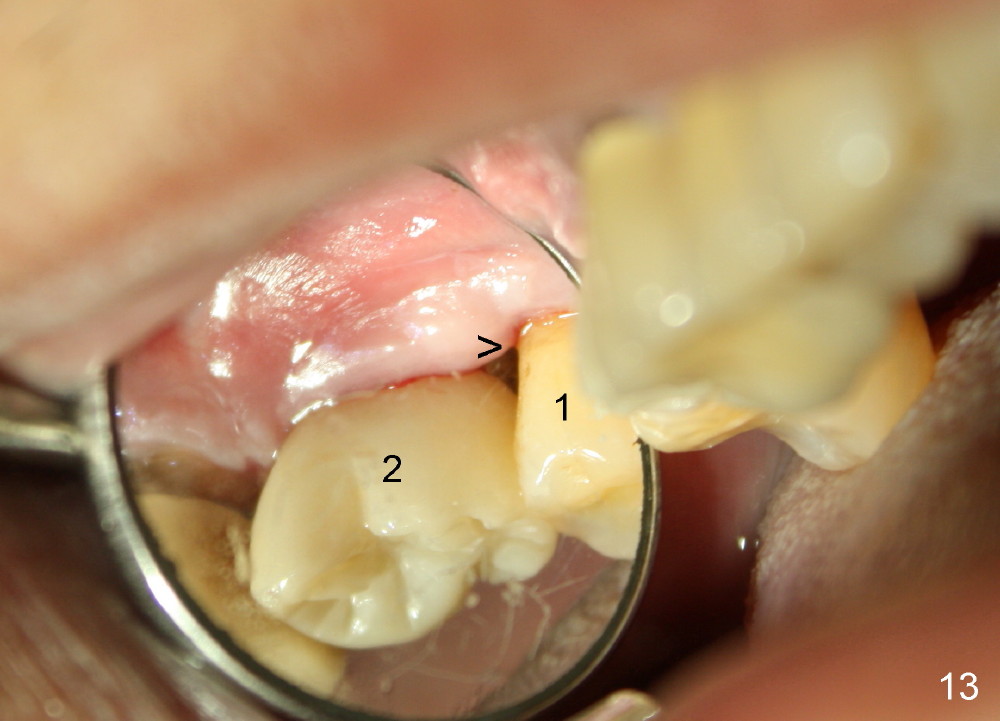

Six months post cementation, the patient returns for follow-up (Fig.11-14) with chief complaint of food impaction between the upper right last 2 teeth. It is difficult to remove. The distal 2nd thread appears not to be covered by the bone, whereas the mesial one is (compare Fig.11 arrowheads). The buccal gingiva is apparently within normal limit (Fig.12) except the distal (Fig.13 >). The distolingual gingiva recession is much more severe (Fig.14). There are deep pockets with tenderness in the abnormal sites. The tooth #1 has #2 mobility with tenderness. The patient agrees to have it extracted and restored with an implant, since the tooth #32 is functional. Bone graft will be placed in the lingual aspect of the implant at the site of #2.